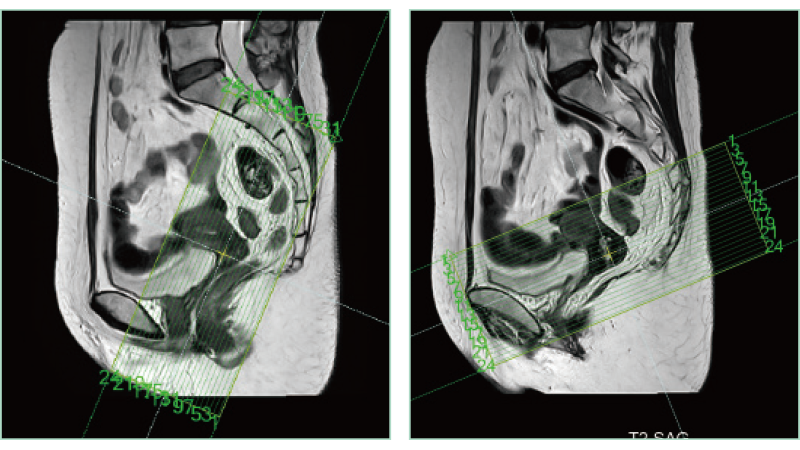

AutoPose Pélvis Feminina

A função de suporte à configuração da linha de corte, "AutoPose", define automaticamente as linhas de corte assim que o escanograma é digitalizado.